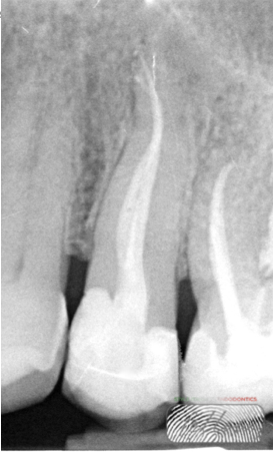

Fig. 2

The X-ray shows the presence of a periapical lesion on tooth 25. Pulp vitality and electric tests were negative.